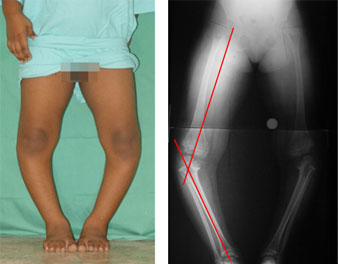

The deformity in the proximal tibia was corrected using the gradual correction using Ilizarov ring fixator and hinges.

The picture on the right side shows correction achieved in terms of the angle and length. The fuzzy appearance in the bone gap is due to the formation of new bone in the gap. |